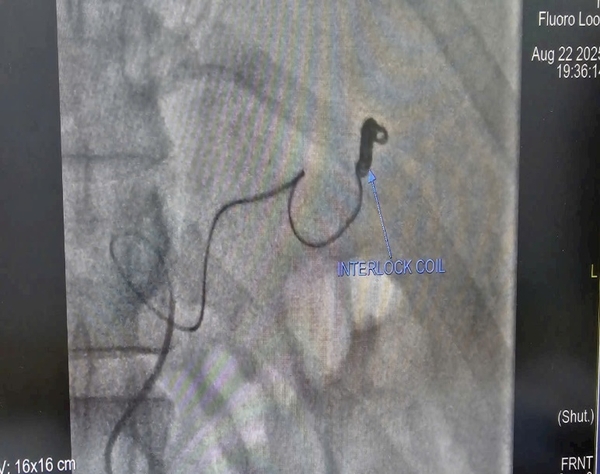

-    Sử dụng coil theo kỹ thuật “Sandwich” để nút tắc đoạn động mạch mang giả phình.

Kết quả sau can thiệp: ổ giả phình được bít tắc hoàn toàn, nhu mô lách vẫn được nuôi dưỡng nhờ hệ bàng hệ. Sau 24 giờ, tình trạng bệnh nhân ổn định, không còn dấu hiệu mất máu, dẫn lưu ổ bụng ra khoảng 2 lít máu cũ.